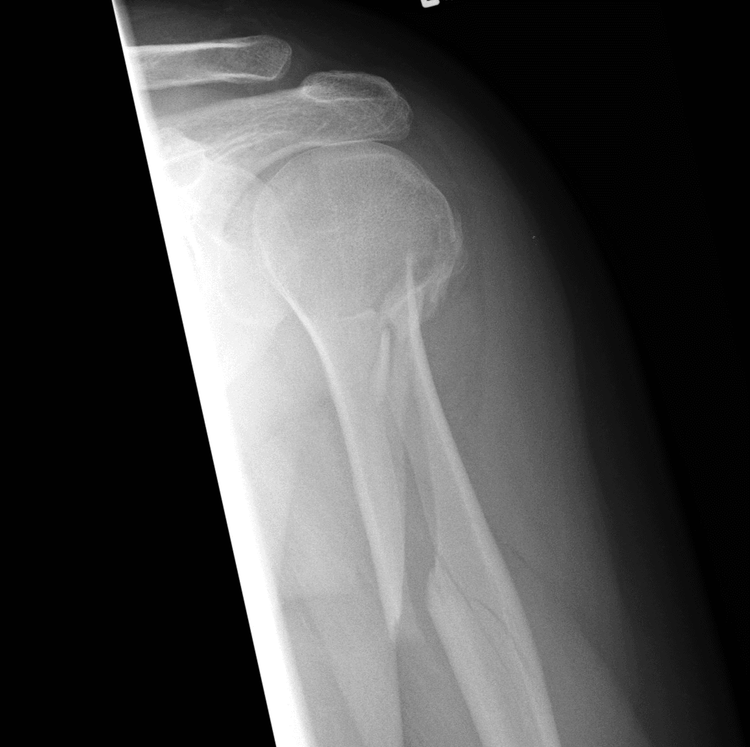

Fracture Dislocation - सांध्यातील एका हाडाला फ्रॅक्चर असल्याने सांधा निखळणे.

Impacted Fracture - एखादे हाड तुटते तेव्हा त्या हाडाचा हिस्सा दुसऱ्या हाडांमध्ये घुसण्याची स्थिती.

IntraArticular Fracture - हाडासोबतच सांध्याचा पृष्ठभाग सुद्धा फ्रॅक्चर होणे.